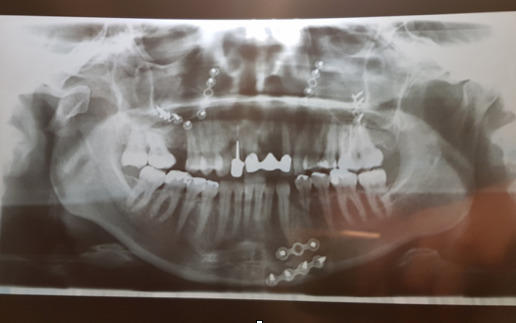

Agnieszka w wyniku uderzenia doznała bardzo poważnych obrażeń. Najbardziej ucierpiała głowa. Lekarze stwierdzili wiele złamań, pęknięć i przesunięć odłamków kości. Od pękniętej podstawy czaszki, poprzez oczodoły, nos, kości jarzmowe, krtań aż po kość gnykową gardła.

Liczne operacje i zabiegi mające na celu ratowanie życia i zdrowia powiodły się. Jednak to dopiero początek drogi Agnieszki. Nadal nie przywrócono podstawowych funkcji zgryzu. Możliwa jest tylko dieta papkowata, utrudniona jest wymowa, a pozostawione do zachowawczego zrostu złamania powodują dysfunkcje, ból i zniekształcenie twarzy. Konieczna będzie rekonstrukcja stawu skroniowo-żuchwowego. To kosztowny, długotrwały i kilkuetapowy proces leczenia, który potrwa od 3 do 4 lat. Tego typu rekonstrukcje nie są refundowane, są też rzadko wykonywane w Polsce. Koszt całego leczenia to kwota od 350 do 400 tys. zł.

Rekonstrukcja powinna odbyć się maksymalnie do 12 miesięcy od wypadku, ze względu na odbywającą się cały czas przebudowę kości w obrębie złamanego i przemieszczonego stawu skroniowo-żuchwowego twarzoczaszki. Zostało więc naprawdę niewiele czasu! Zaledwie dwa miesiące…